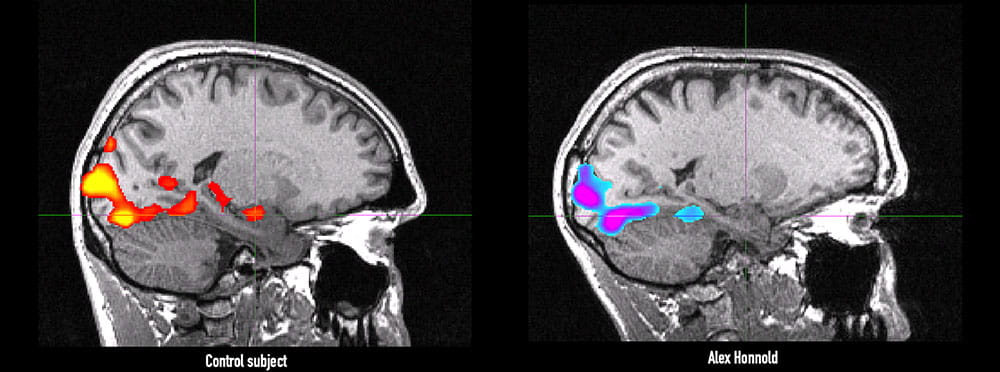

Alex Honnold's brain scan versus a control brain scan

FMRI imaging shows amygdala activity in a control subject, left, and Honnold, right, when looking at images expected to elicit emotional responses from the viewer. Images courtesy of Dr. Jane Joseph

Compared against the data pool Joseph already had — she had even recruited a rock climber roughly Honnold’s age to come in and go through everything he did — Honnold turned out to be twice as sensation-seeking as the average person and 20 percent higher than the average high-sensation seeker.

“My take on it is there are probably some stimuli that would activate his amygdala, but if you just compare him to the norm or baseline, he does not show anything,” she said. “That said, Alex scored pretty high on the trait of conscientiousness, which has shown to protect against becoming addicted and getting into that spiral.”